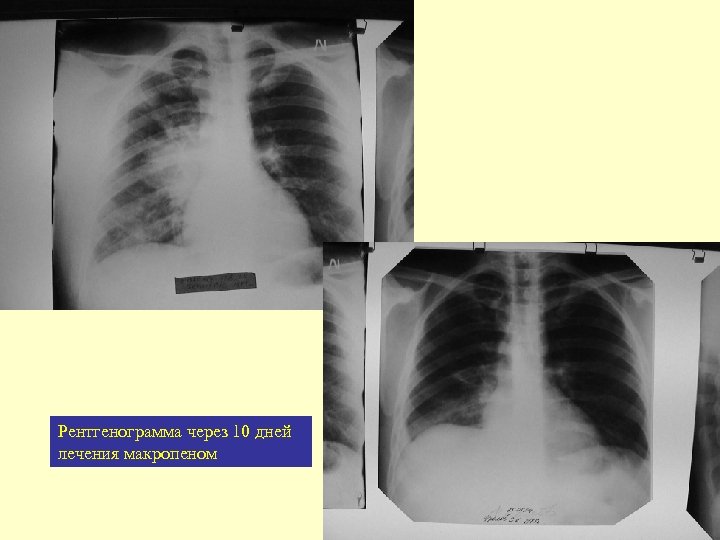

Монотерапия per os

Рентгенограмма через 10 дней лечения макропеном